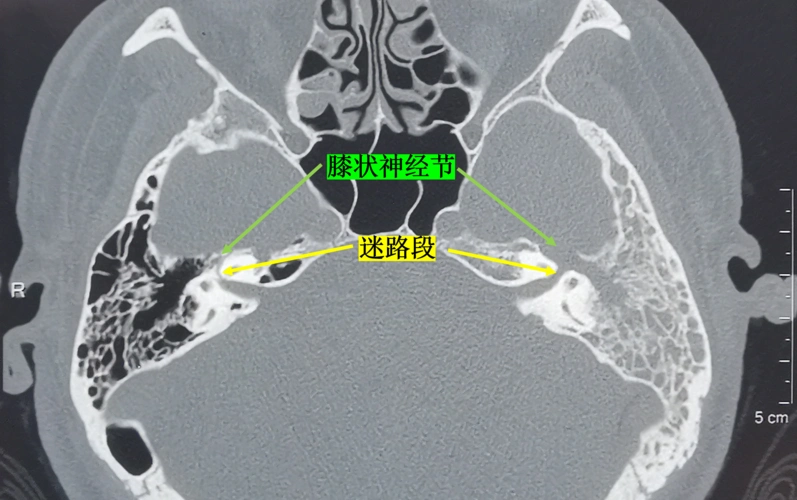

面神经解剖与常见疾病

面神经瘤的影像学特点